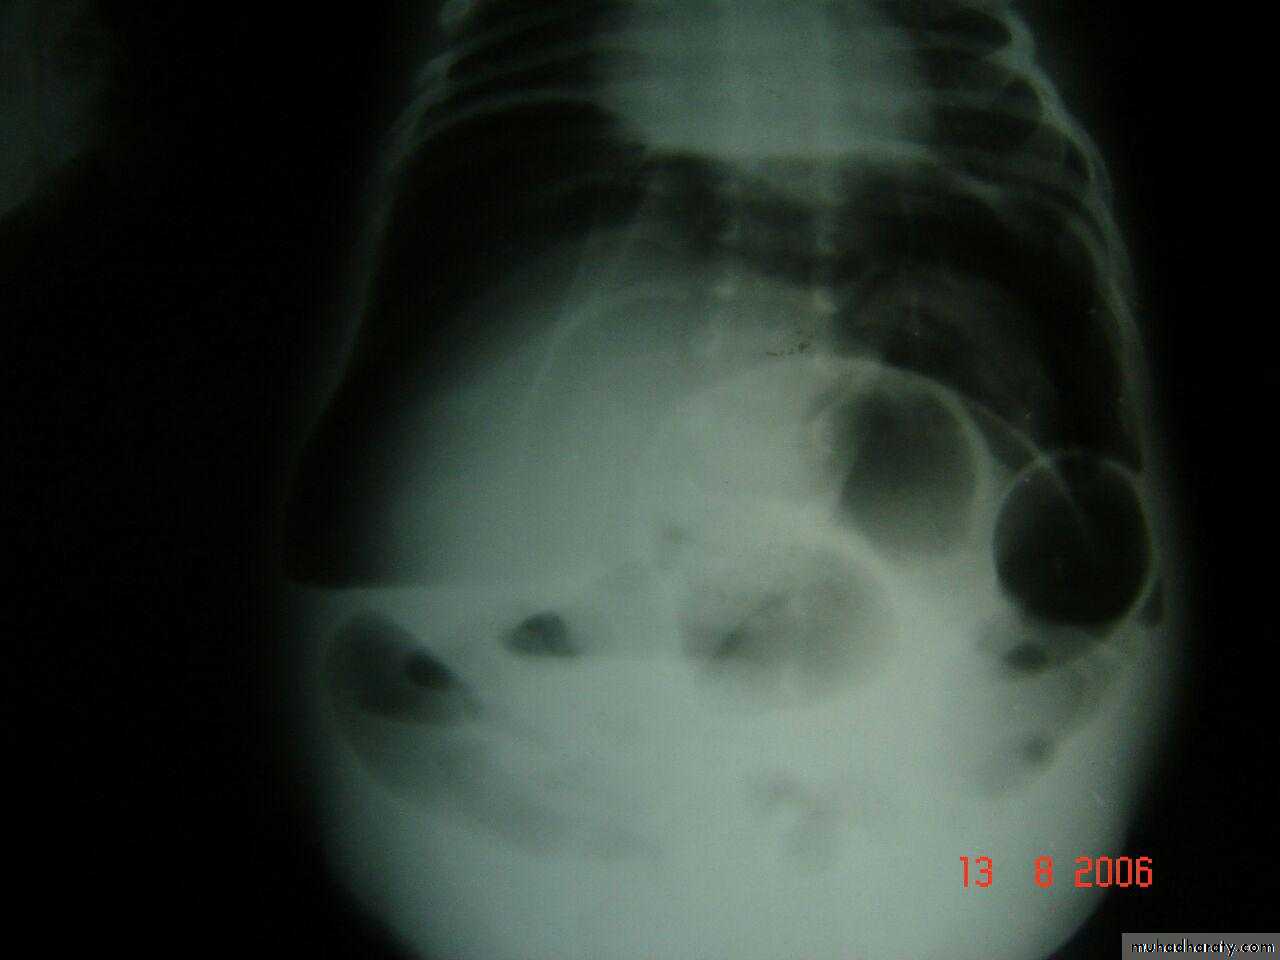

( coil spring sign )Coil spring sign intussusseption

3 signs >> current jelly stool

Suscage mass

Prolapse of the mass theough rectum

3 bubble apperance of jujenal atresia

Double bubble apperance of dudenal atresia